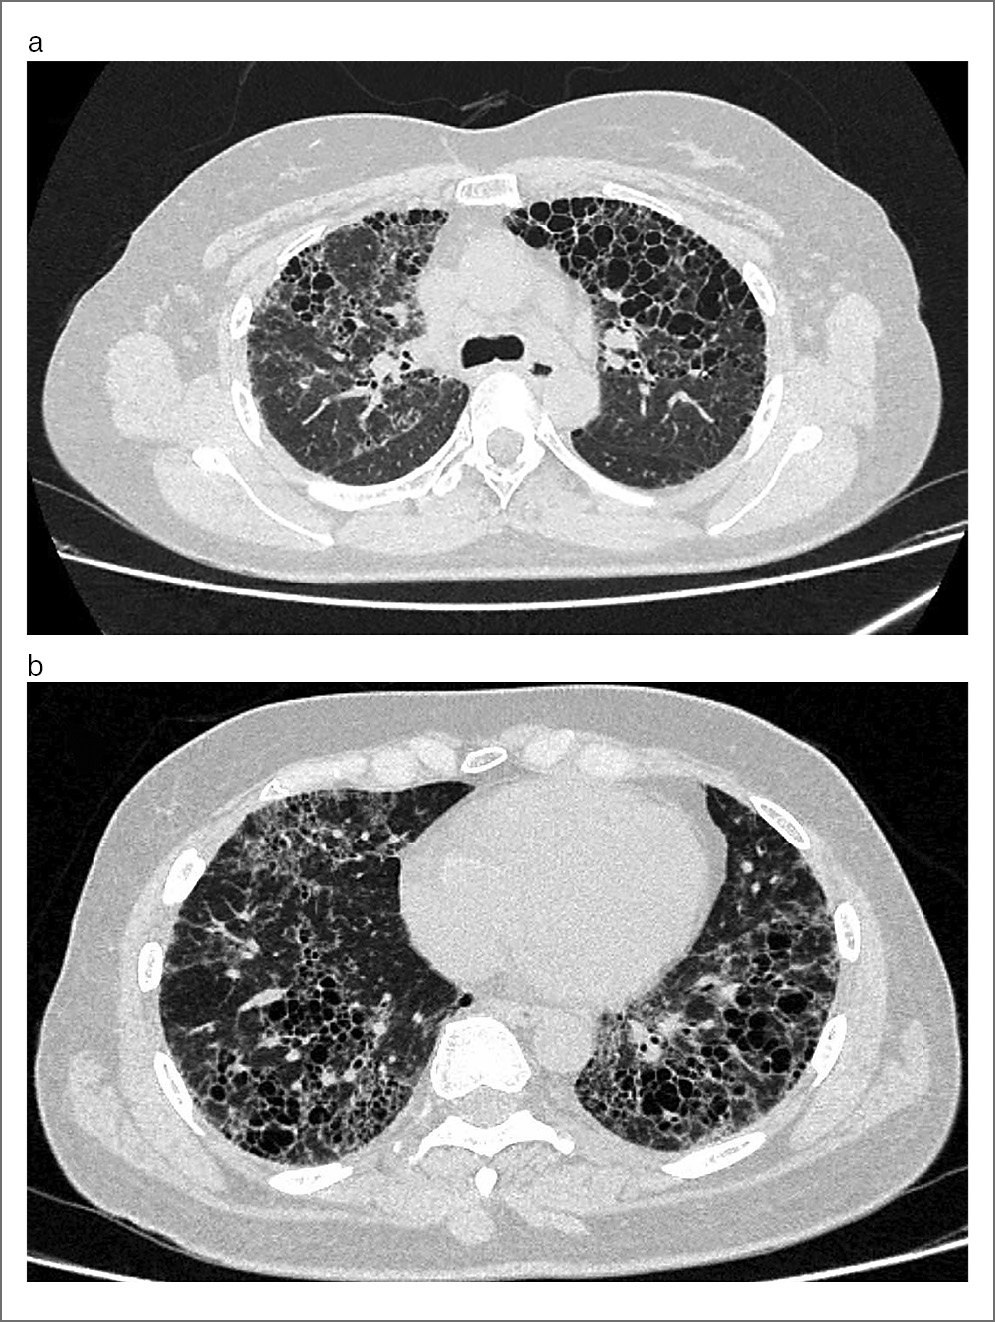

Ретикулярные изменения оказались наиболее типичными для фГП и выявлены у 49 (94,2%) лиц. Большая часть пациентов имели 1-ю степень выраженности изменений – 34 (65,4%) человека, у 11 (21,2%) наблюдалась 2-я степень выраженности, у 3 (5,8%) пациентов обнаружена 3-я степень выраженности, и у 1 (1,9%) – 4-я степень. Это означает, что распространенные диффузные ретикулярные изменения нетипичны для фГП. Распределение ретикулярных изменений также имело свои особенности. Так, отмечено преобладание в кортикальных и субплевральных отделах легких с преобладанием в нижних долях обоих легких, несколько реже – в центральных и прикорневых отделах, как показано на рис. 2.

Рис. 2. Женщина, 61 год, фГП: a – аксиальный срез демонстрирует множественные линейные участки уплотнения различной протяженности и сетчатые структуры, что соответствует картине ретикулярных изменений. Большая часть подобных структур определяется на фоне участков «матового стекла» (симптом «хаотичного мощения»); b – реформация во фронтальной проекции показывает на преимущественно нижнедолевое распределение ретикулярных изменений. В субплевральных отделах определяются единичные участки пониженной плотности, что соответствует картине «мозаичной плотности».